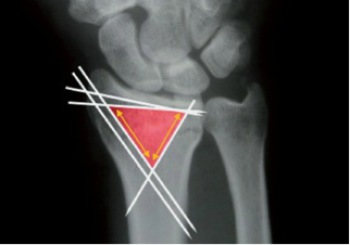

LAS FRACTURAS DE RADIO PLANTEAN UN  RETO PARA EL CIRUJANO ORTOPÉDICO

Existe desde hace más de 100 años un método conservador descrito por Colles que durante tantos años fue aceptado como patrón de tratamiento. Ya ha cambiado la forma de reducción e inmovilización y para dar solución a las fracturas más inestables de forma quirúrgica.

Los pacientes con fracturas tipo A2, B1 y C1, con agujas de Kirschner (AK) de 1,8 mm de diámetro

Las fracturas extraarticulares, sin gran conminución metafisaria  y fracturas intraarticulares simples con buena reserva ósea. Muy malos resultados en fracturas muy conminutas o aquellas con fragmentos volares